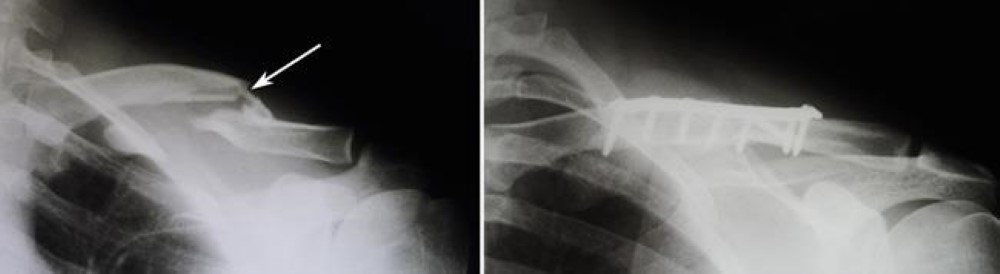

Internal fixation of clavicle fracture

(Left) X-ray shows a severely displaced clavicle fracture (arrow). (Right) Here, a single screw has been used to repair the fracture.

Reproduced from Eichinger JK, Balog TP, Grassbaugh JA: Intramedullary fixation of clavicle fractures: anatomy, indications, advantages, and disadvantages. J Am Acad Orthop Surg 2016; 24(7): 455-464.